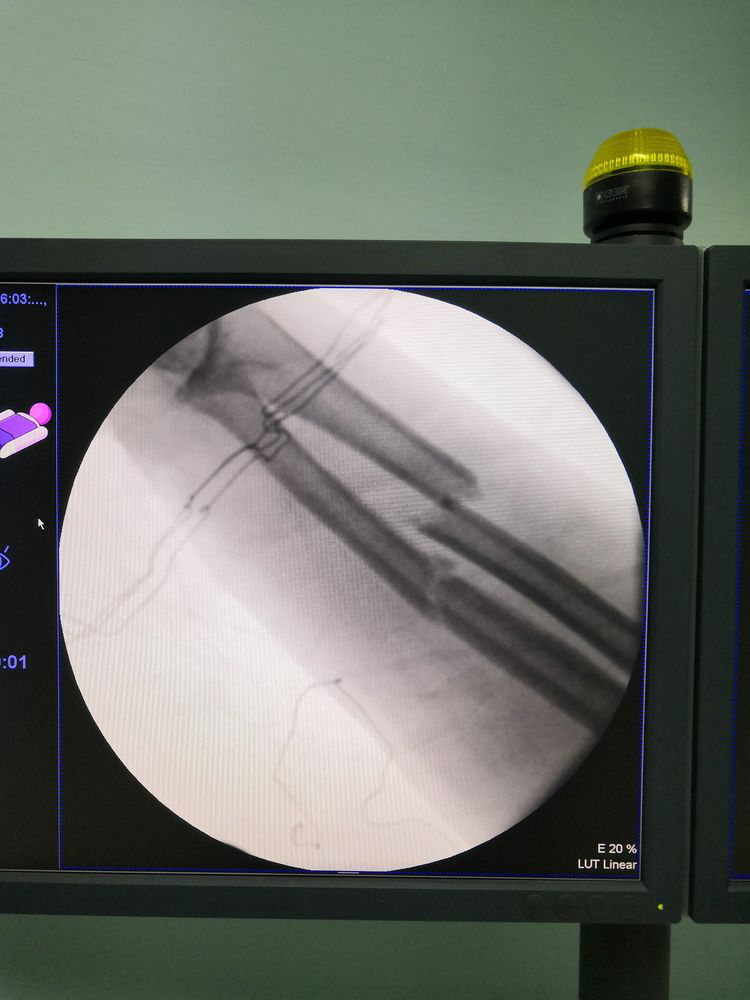

术中透视见尺桡骨中段骨折

手术由骨科二病区刘磊主治医师和魏春生主任共同完成。术中除常规清创、克氏针固定拇指指骨、修复受损肌腱外,还在10倍显微镜下进行了血管、神经等精细组织的吻合,手术顺利,目前患者正在康复中。